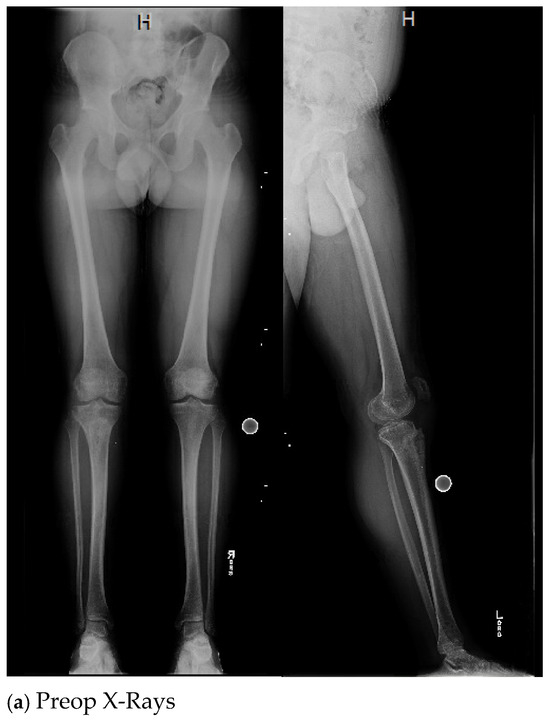

| 4. | 75 | F | Y | N | 20 | N | N | 17 | Right thigh and gluteal abscess with infected right femoral neck hardware and osteomyelitis |